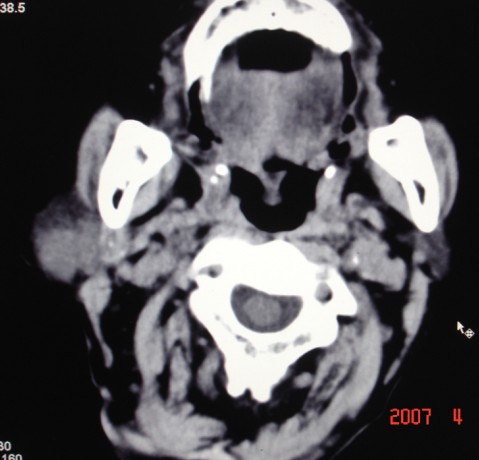

以下是引用zjzjr在2007-4-9 13:27:00的发言:[br]右侧腮腺深浅叶可见一混杂密度区,含有实性及囊性成.考虑右侧腮腺混合瘤,建议ct增强扫描。

以下是引用jiangjing在2007-4-9 15:09:00的发言:[br]考虑右侧腮腺肿瘤[混合瘤可能性大],其他待排[br]建议ct增强扫描。